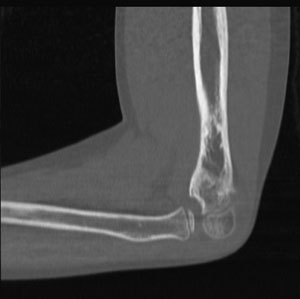

Elbow-CT.jpgThe scientific unit of measurement for radiation dose is the Gray (Gy), which is a measure of the amount of X-ray energy absorbed per unit mass. Other radiation units include rad, rem, roentgen, and Sievert.